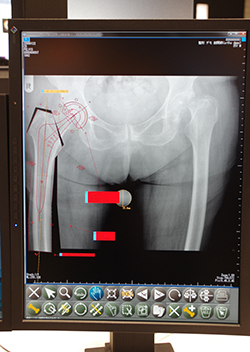

整形外科用PACS「iRad-OT」

iRad-OTは整形外科向けのPACSである。Sharp角やCobb角などの自動計測が可能なほか,高度な計測にも対応している。システム内に主要なインプラントメーカーの製品情報が収録されており,手術に用いるインプラントを選択し,画像上に重ね合わせてシミュレーションできる。このインプラント情報は定期的に更新される。ブース内では,iRad-OTと組み合わせて,人工関節の摩耗度や膝軟骨の定量評価を行えるソフトウエアの「Dr.View/LINUX」も紹介された。

精度の高い整形外科手術を支えるiRad-OT